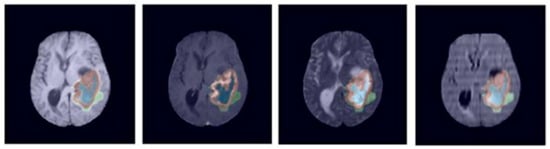

259 glioma images of higher grade and 76 lower grade images are included in the BraTS 2019 data, the manual creation of a ground truth by the expert neuroradiologists is utilized for the annotation protocol. In the database, the MRI scans belong to 4 modalities, such as T1, T2, T2-CE, and T2-FLAIR, and example scans are given in Figure 4.

Figure 4.

Sample MRI brain scans of BraTS 2019 database [36].